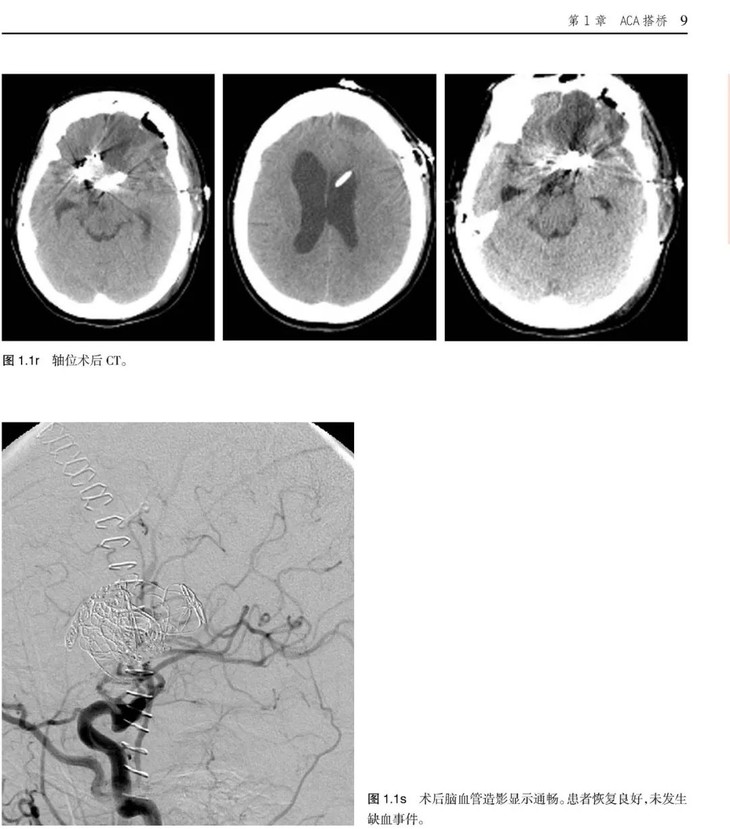

《脑血运重建彩色图谱:解剖、技巧及病例》主要介绍了脑血运重建手术的各种技巧和临床应用。这项技术是世界著名的亚利桑那州凤凰城巴罗神经病学研究所的外科医生首创的。每个步骤都以术中照片及精美的解剖图呈现,以帮助神经外科医生掌握复杂的显微外科解剖及微妙的外科技巧,从而用于治疗脑卒中潜在发作以及其他脑缺血疾病。

•描述了如何成功实施诸如烟雾病、血管内治疗后复发动脉瘤、巨大动脉瘤,以及椎动脉供血不足及重度狭窄的脑血运重建